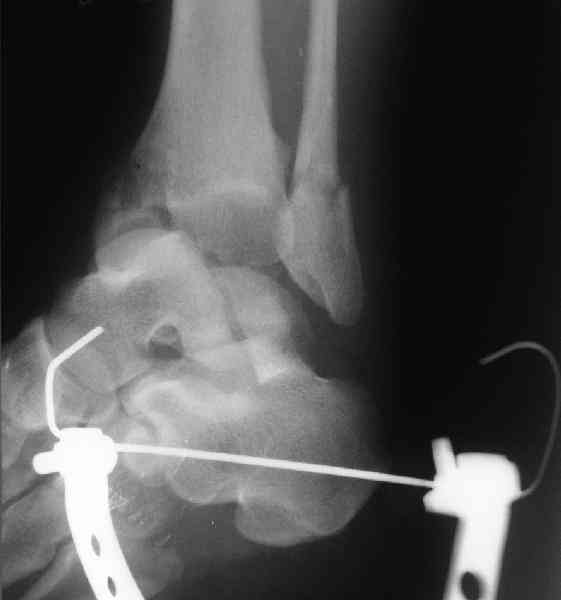

Для оценки состояния нужны дополнительные исследования, например

> Canale или Broden ренгенограммы

повторили рентгенограммы и доделали проекции, к единому мнению все еще не пришли